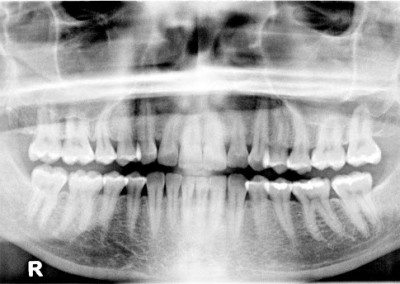

On the left side, teeth #11 and #12 have a notched abfraction and strong recession. The right side shows recession on #3, #4, #5, and #30. This is a maxilla to mandible skeletal asymmetry case that has had a lifetime of sinus issues. The upper arch is the shape of a “V” and the mandible has a “U” shape. A “U” does not fit inside of a “V” so the force scans will find the unbalanced pattern.

Notice the full face picture and how the labial fold is different on the left versus the right. This is diagnostic to what we see inside the mouth. Her left maxilla is narrow and not symmetrical to the right maxilla. The midline of the centrals is left of center and the periodontal tissue change at the distal of #9 and do not return to normal until tooth #13. Many patients have periodontal changes as a result of a skeletal growth asymmetry in growth. Chronic allergies as a child had a strong influence on vaulting the palate. The maxilla has a “V” shape as a result and the mandible grew in a more normal “U” shape.

The patient has had issues with her jaw and neck that started with a 1995 auto accident. Patient states “I have had TMJ since 1995 and my jaw is constantly moving. What can I do?” A California dentist made a lower splint in 1995 that was worn for 5 years. The narrow growth pattern of the maxillary bones are more than likely due to childhood allergies. Functionally speaking, the bones and the teeth are not aligned well for optimum function. The teeth are in good condition, so the periodontal and referring pain patterns are the primary concern.